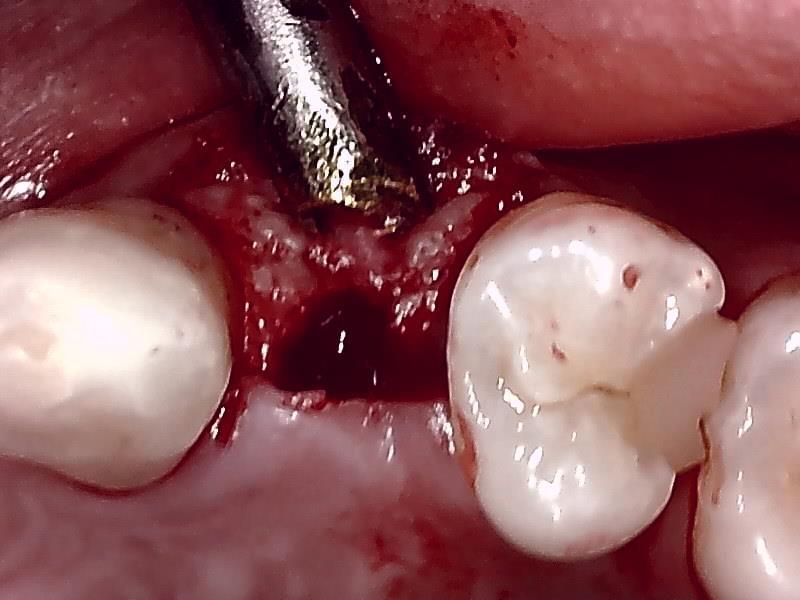

ドリリング

顎堤部 歯槽骨にドリリングする。

インプラント体の口径に合わせて埋入孔を形成した状態です。